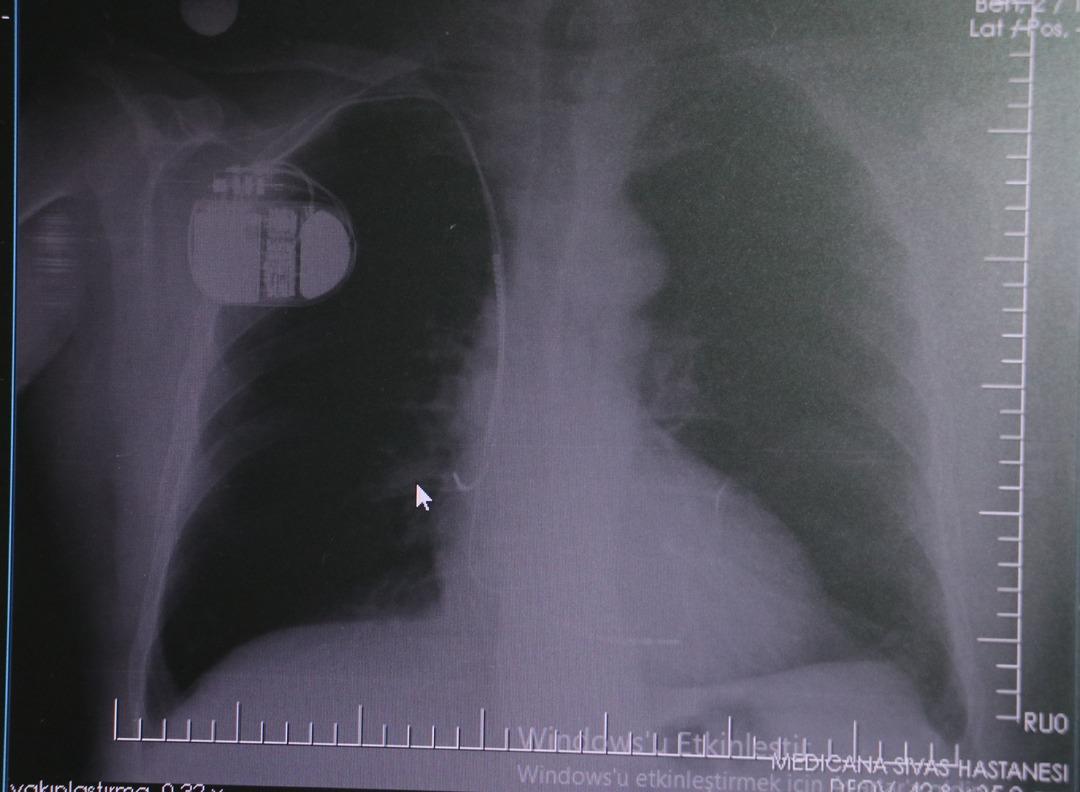

MR makinesine kalp pili takılmasının mümkün olduğunu belirten Erdoğu, şöyle konuştu: “Çok büyük bir ameliyat değil ama yine de ciddi bir cerrahi işlem. Kalp pili tıpta son 30 yılın en büyük gelişmesi. Aslında bilgisayarın minyatürleştirilmiş hali olup insan vücuduna yerleştirilen bir tedavi. İnsan ömrünü önemli ölçüde uzatan bir tedavi. İnsanlar şokla hayata tutunurken, pil olmasaydı öleceğini düşündüğümüz çok sayıda hastamız var. Bu özelliğimiz Kalp pili uygun hastalarda ani ölümü önler, ritmi düzeltecek sağlık çalışanı veya defibrilatör yoksa hastayı hayatta tutmak mümkün değildir. Hastalarımız “kalp pilim var” dediğinde hastalıktan kurtulurlar. Örneğin, mikser kullanmak veya kolu sallayacak herhangi bir hareket kalp pilini olumsuz etkileyebilir. Soğuk havalarda vücutta meydana gelen şiddetli titremeler kalp pilinin hafızasını karıştırıp gereksiz şoklara neden olabilir.